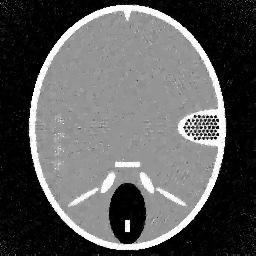

(d)

Figure 4. Results of different methods for reconstructing the gel phantom with underdetermined rate 77%. (a) FBP, (b) L2-TV with scalar λ𝜆\lambda, (c) Our method, (d) λ𝜆\lambda in our method.

Figure 5. Results of different methods for reconstructing the gel phantom with underdetermined rate 38%. (a) FBP, (b) L2-TV with scalar λ𝜆\lambda, (c) Our method, (d) λ𝜆\lambda in our method.

Example 2. Additionally to the simulated data, we also test our method on real CT measurements. In this experiment the gel phantom shown in Figure 1 (b) is measured using a fan-beam geometry with 560 beams and 360 or 180 projection angles. The reconstructions are in a square domain of 512×\times512 pixels, which result in an under-determined rate of 77% and of 38%, respectively.

In Figure 4 and 5 we compare our method with the FBP algorithm and the L2-TV method. Due to insufficient measurements and noise, FBP cannot provide satisfactory results. Comparing the results obtained by our method with the ones from the L2-TV method, we see that our method reduces more artifacts while keeping similar quality on reconstructed object textures. Furthermore, from the final values of λ𝜆\lambda obtained in our method we find that our method can correctly distinguish textured regions from homogeneous regions. Then, by setting different regularization parameter values, we vary the strength of the smoothness in the different regions.